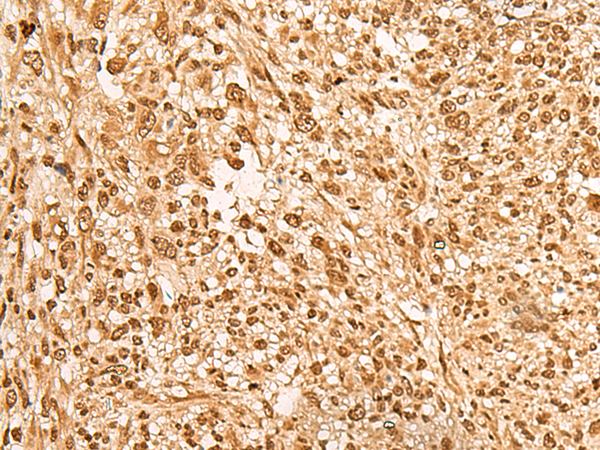

分类: 科研抗体货号: P09848别名: L11; HN1L; C16orf34应用: IHC反应种属: Human